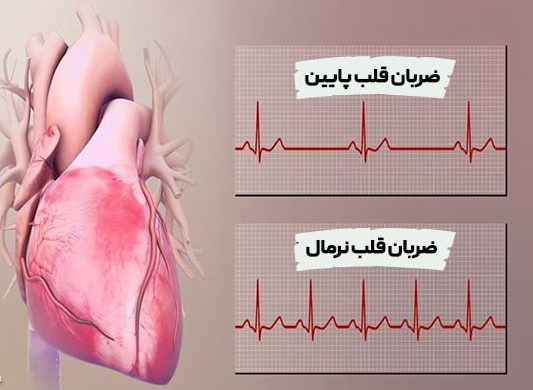

علائم زخم معده را با حملهقلبی اشتباه نگیرید

نکته مهمی که باید در نظر گرفت این است که علائم حمله قلبی گاهی میتواند مشابه زخم معده و مشکلات گوارشی باشد. در صورت تجربهی نشانههایی مانند سوزش سر دل، درد منتشرشونده به شانه یا کتف، و حالت تهوع، لازم است فوراً با پزشک مشورت کنید تا سلامت قلب شما ارزیابی شود. در چنین شرایطی از خوددرمانی خودداری کرده و تشخیص نهایی را به پزشک متخصص بسپارید.